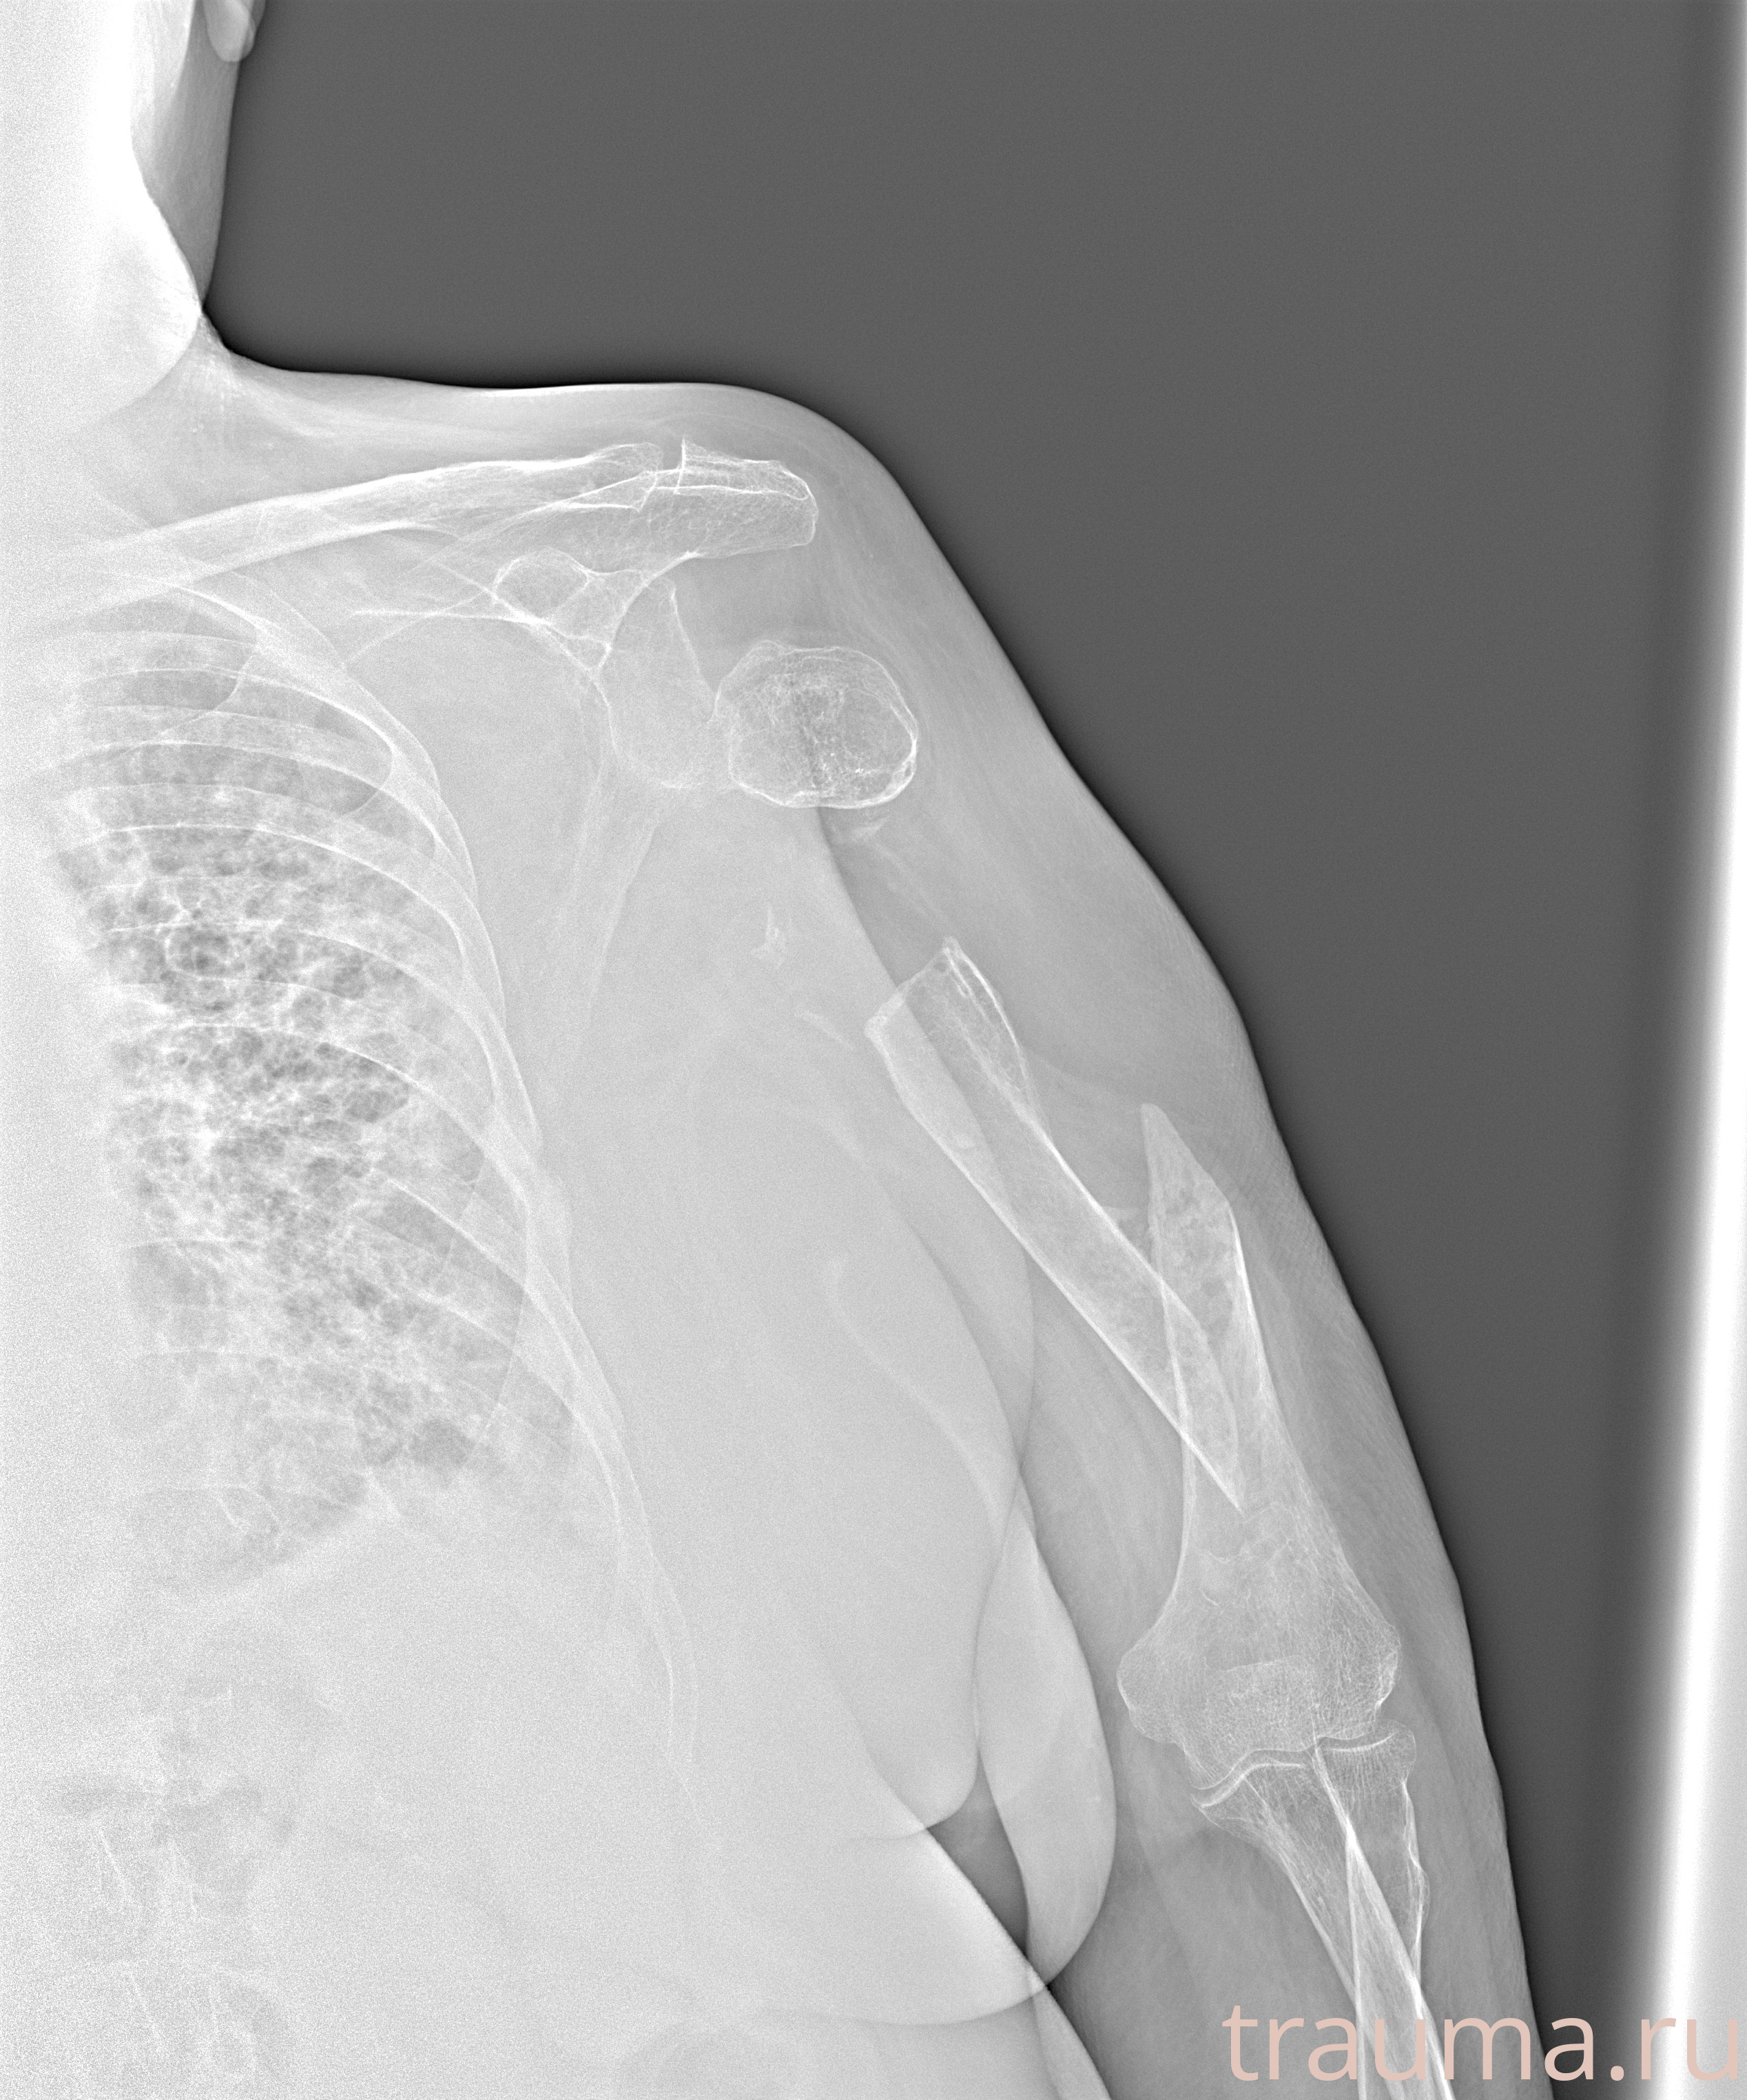

Рентген на дому: по вашему адресу приезжает врач-рентгенолог, травматолог-ортопед с мобильным рентгеновским аппаратом, проводит диагностику травмы или заболевания, делает необходимые рентгенограммы, дает рекомендации по дальнейшему лечению. Получить качественные снимки в домашних условиях возможно благодаря уникальной методике, разработанной МосРентген Центром для института  Склифосовского

при переломе шейки бедра и пневмонии от компании МосРентген Центр - партнера Института имени Склифосовского